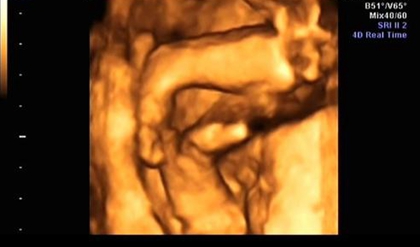

网上有一种说法是,在做四维彩超的时候,如果是女宝宝是比较不容易配合的,如果是男宝宝更容易通过,那么是不是四维女宝更容易配合呢,四维女宝特征有哪些?

很多网上的说法是女宝宝在做B超检查的时候更不容易配合,其实这种说法是没有依据的,宝宝在妈妈肚子里的时候会胎动,也会自己变换姿势,这是正常的,宝宝不配合和性别是没有关系的,如果做四维的时候想要让宝宝配合,那么就要想办法咯。